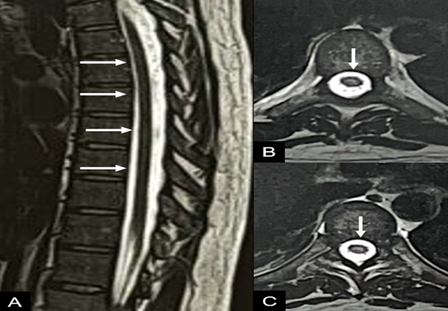

Figure 1: sagittal (a) and

axial (b) t2-weighted images of the thoracic spine, showing a slight area of

signal alteration in the central portion of the spinal cord (arrows in a and

b).